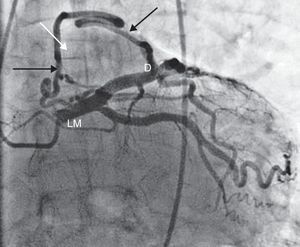

Case reportA 62-year-old man was admitted to our hospital with sudden development of general weakness, dizziness and a sensation of compression in his chest. He had a history of diabetes mellitus. At presentation his blood pressure was 80/40 mmHg and heart rate was 65 beats/min. The ECG revealed sinus rhythm and 1–2 mm ST elevation in the anterior leads (Figure 1). The patient was taken to the catheterization laboratory for percutaneous coronary intervention. The left main and left circumflex coronary arteries were normal. Coronary angiography showed a communication between the left main and the diagonal branch of the left anterior descending and a fistula between the intercoronary connection and the left atrium (Figure 2). The other coronary arteries were normal. Laboratory test results, including cardiac troponin I and creatine kinase–MB levels, were normal. The angina symptoms disappeared and the ST elevation resolved within four hours (Figure 3). To the best of our knowledge, this is the first case in the literature involving a congenital coronary artery fistula in an intercoronary communication.